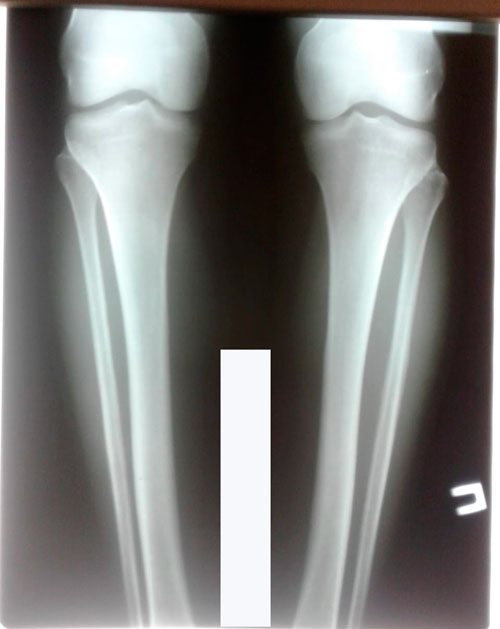

Исходник - 31 год. Уральск.

Дата операции - 25.09.2018г.

Перед крутками

ножки на сращении.